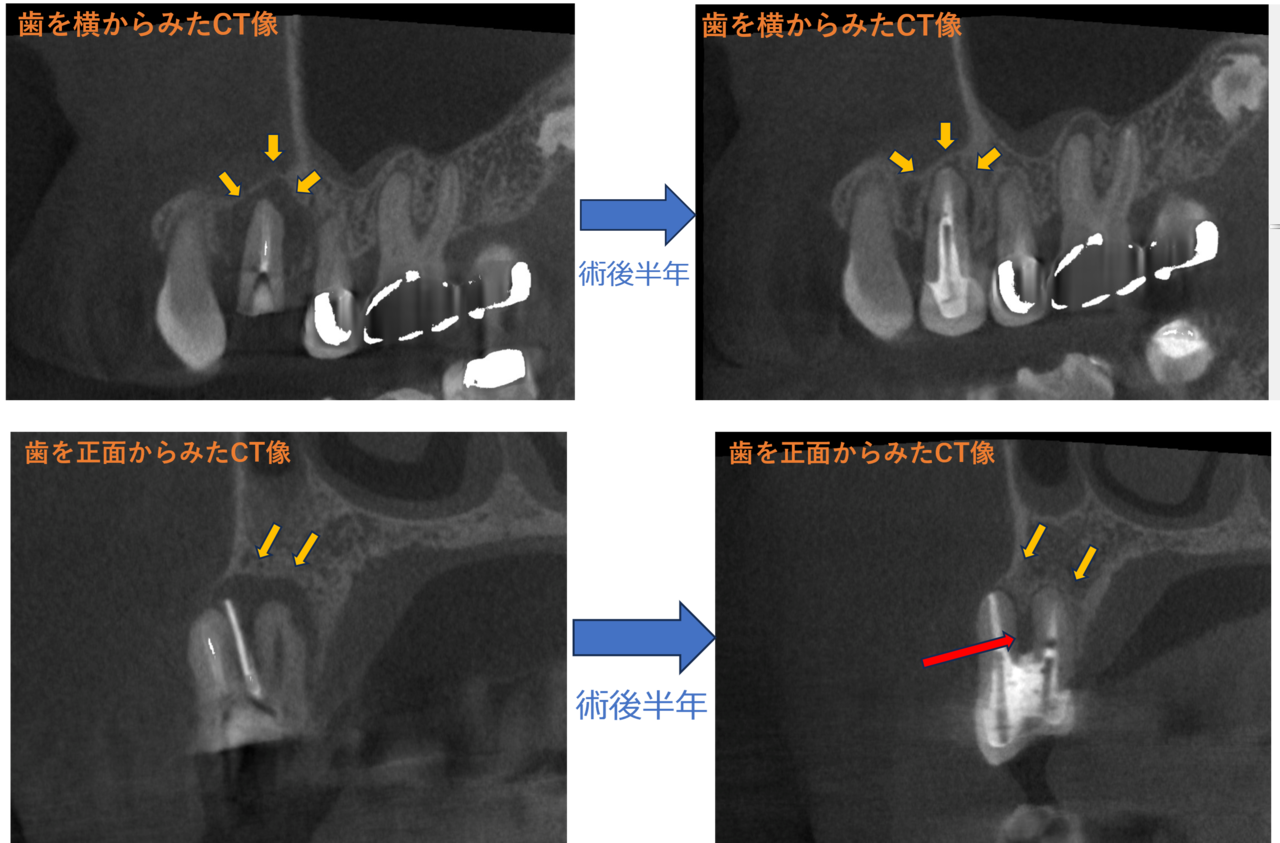

術後半年

CBCTを撮影しました。症状はありませんでしたが根管治療の予後は、(具体的には骨吸収した部位の回復)は様々で完全治癒の場合もあれば、部分的に治癒、全く治癒していない場合もあります。私は患者さんとご相談させて頂いた上で、予後をご説明させて頂くために症状がなくてもで撮影する場合があります。

運が良く想像以上に骨も回復してくれていました(黄色矢印)。ガッタパーチャがとびてていたところがもう少し回復してくれると完璧なのですが(赤矢印)、症状もなく痛みもないとのことで今後も歯根破折など注意して経過観察していきたいと思います。